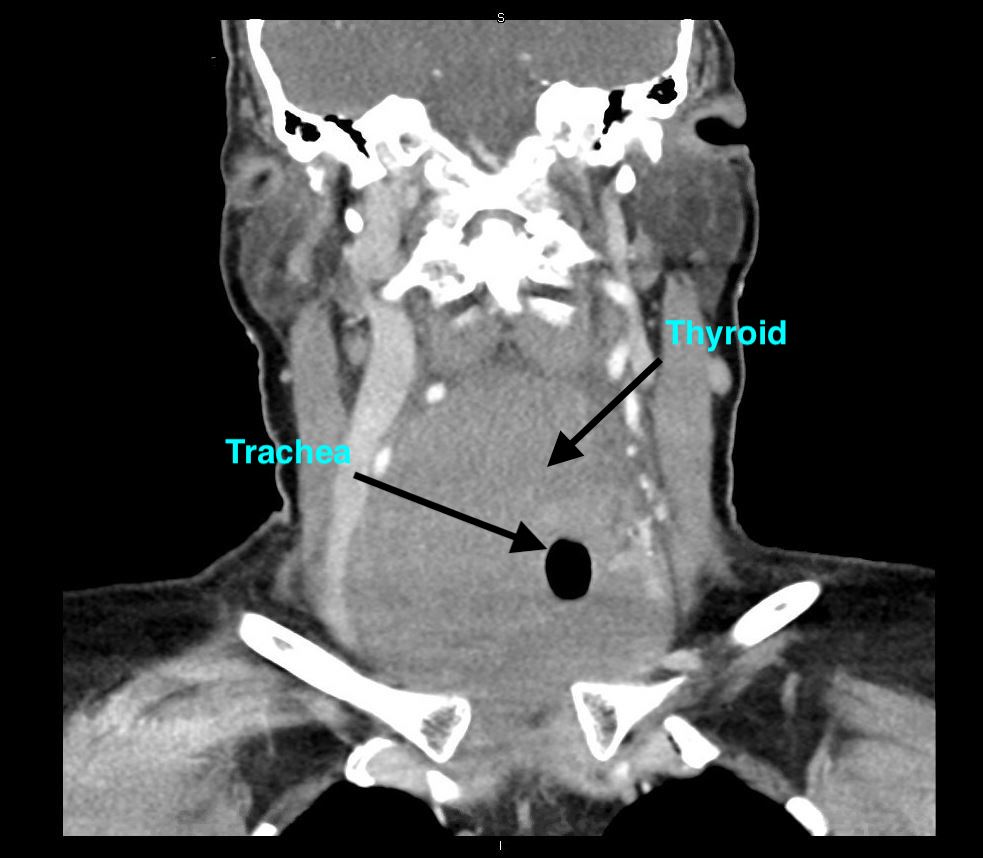

A CT scan of the neck was performed to evaluate the patency of the patient’s airway, and the corresponding images showed a hypodense lesion, which represented the air in trachea, completely surrounded by high-density tissue consistent with thyroid tissue—a radiologic sign that is commonly known as the doughnut sign (Figures).

The subsequent pathology results from the hemithyroidectomy were consistent with diffuse large B-cell lymphoma. The annual incidence of this disease is estimated to be 2.1 per million persons, with a 4 to 1 female predominance.3 The only known risk factor for this condition is preexisting chronic autoimmune thyroiditis. This patient’s case is a very typical presentation of thyroid lymphoma; however, the CT finding of thyroid tissue encasing the trachea is pathognomonic for this condition. She was started on the R-CHOP (rituximab, cyclophosphamide, doxorubicin, vincristine, and prednisone) chemotherapy regimen and has been responsive to therapy.